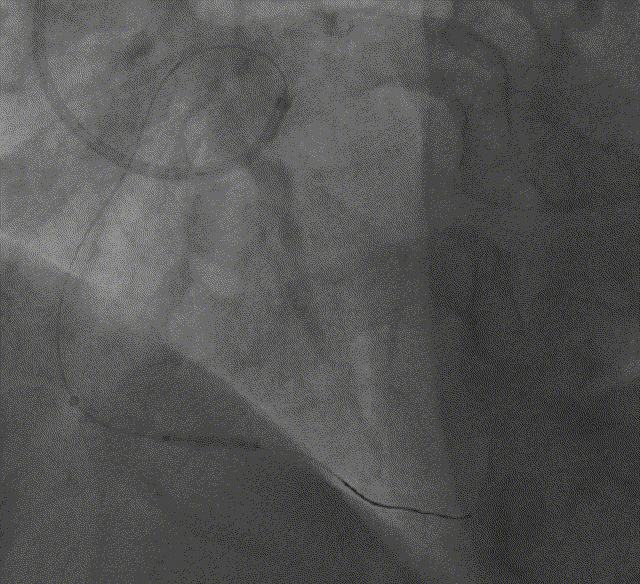

于PL送入SION blue导丝、Tazuna 2.0*15mm球囊扩张PL,Telescope™导引延长导管支持下植入2.5*36mm、3.0*33mm、3.5*36mm支架各一枚

Telescope™导引延长导管支持下植入2.5*36mm、3.0*33mm、3.5*36mm支架各一枚